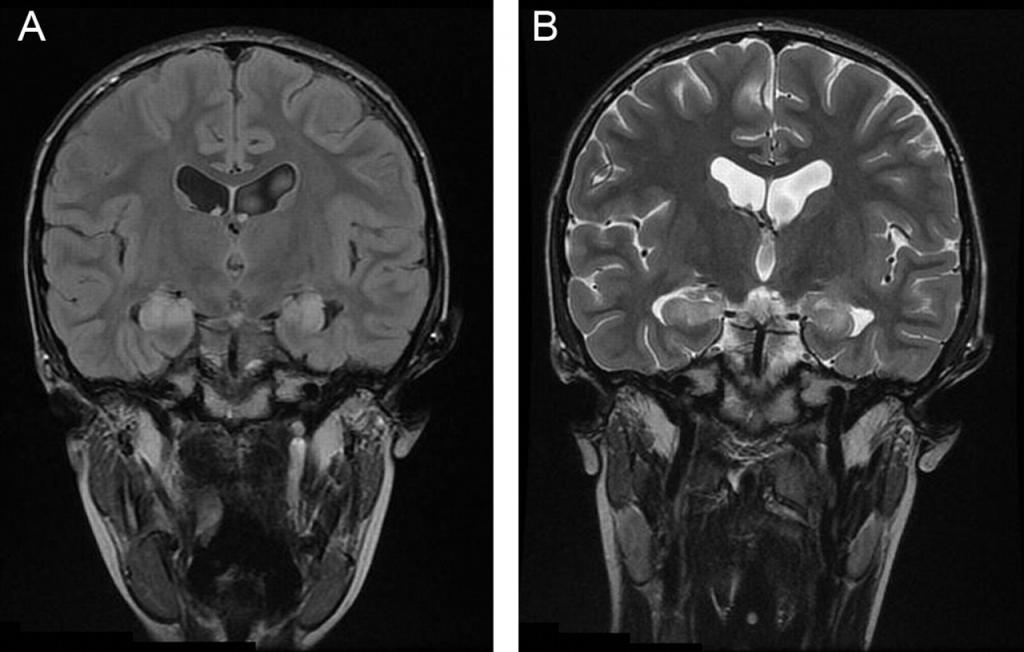

- компьютерная томография (КТ) и магнитно-резонансная томография (МРТ) головного мозга;

- компьютерная томография;

- МРТ и КТ.